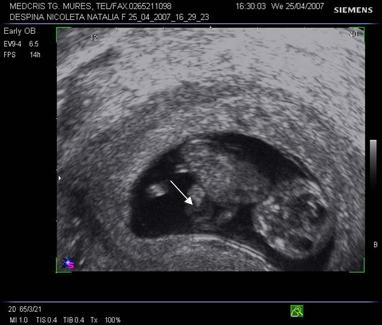

Fig. nr.128 Pliu nuchal cu dimensiunea de 2,9 mm.Cu sageata se remarca alaturat amniosul, magnificatia redusa nu permite obtinerea unei imagini optimale a translucentei nuchale.